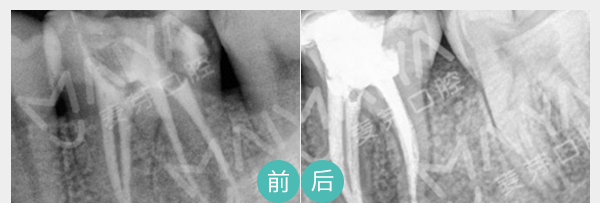

通过机械和化学方法去除根管内的大部分感染物,并通过充填根管、封闭冠部,防止发生根尖周病变或促进已经发生的根尖周病变的愈合。

适应症:牙根尖周炎